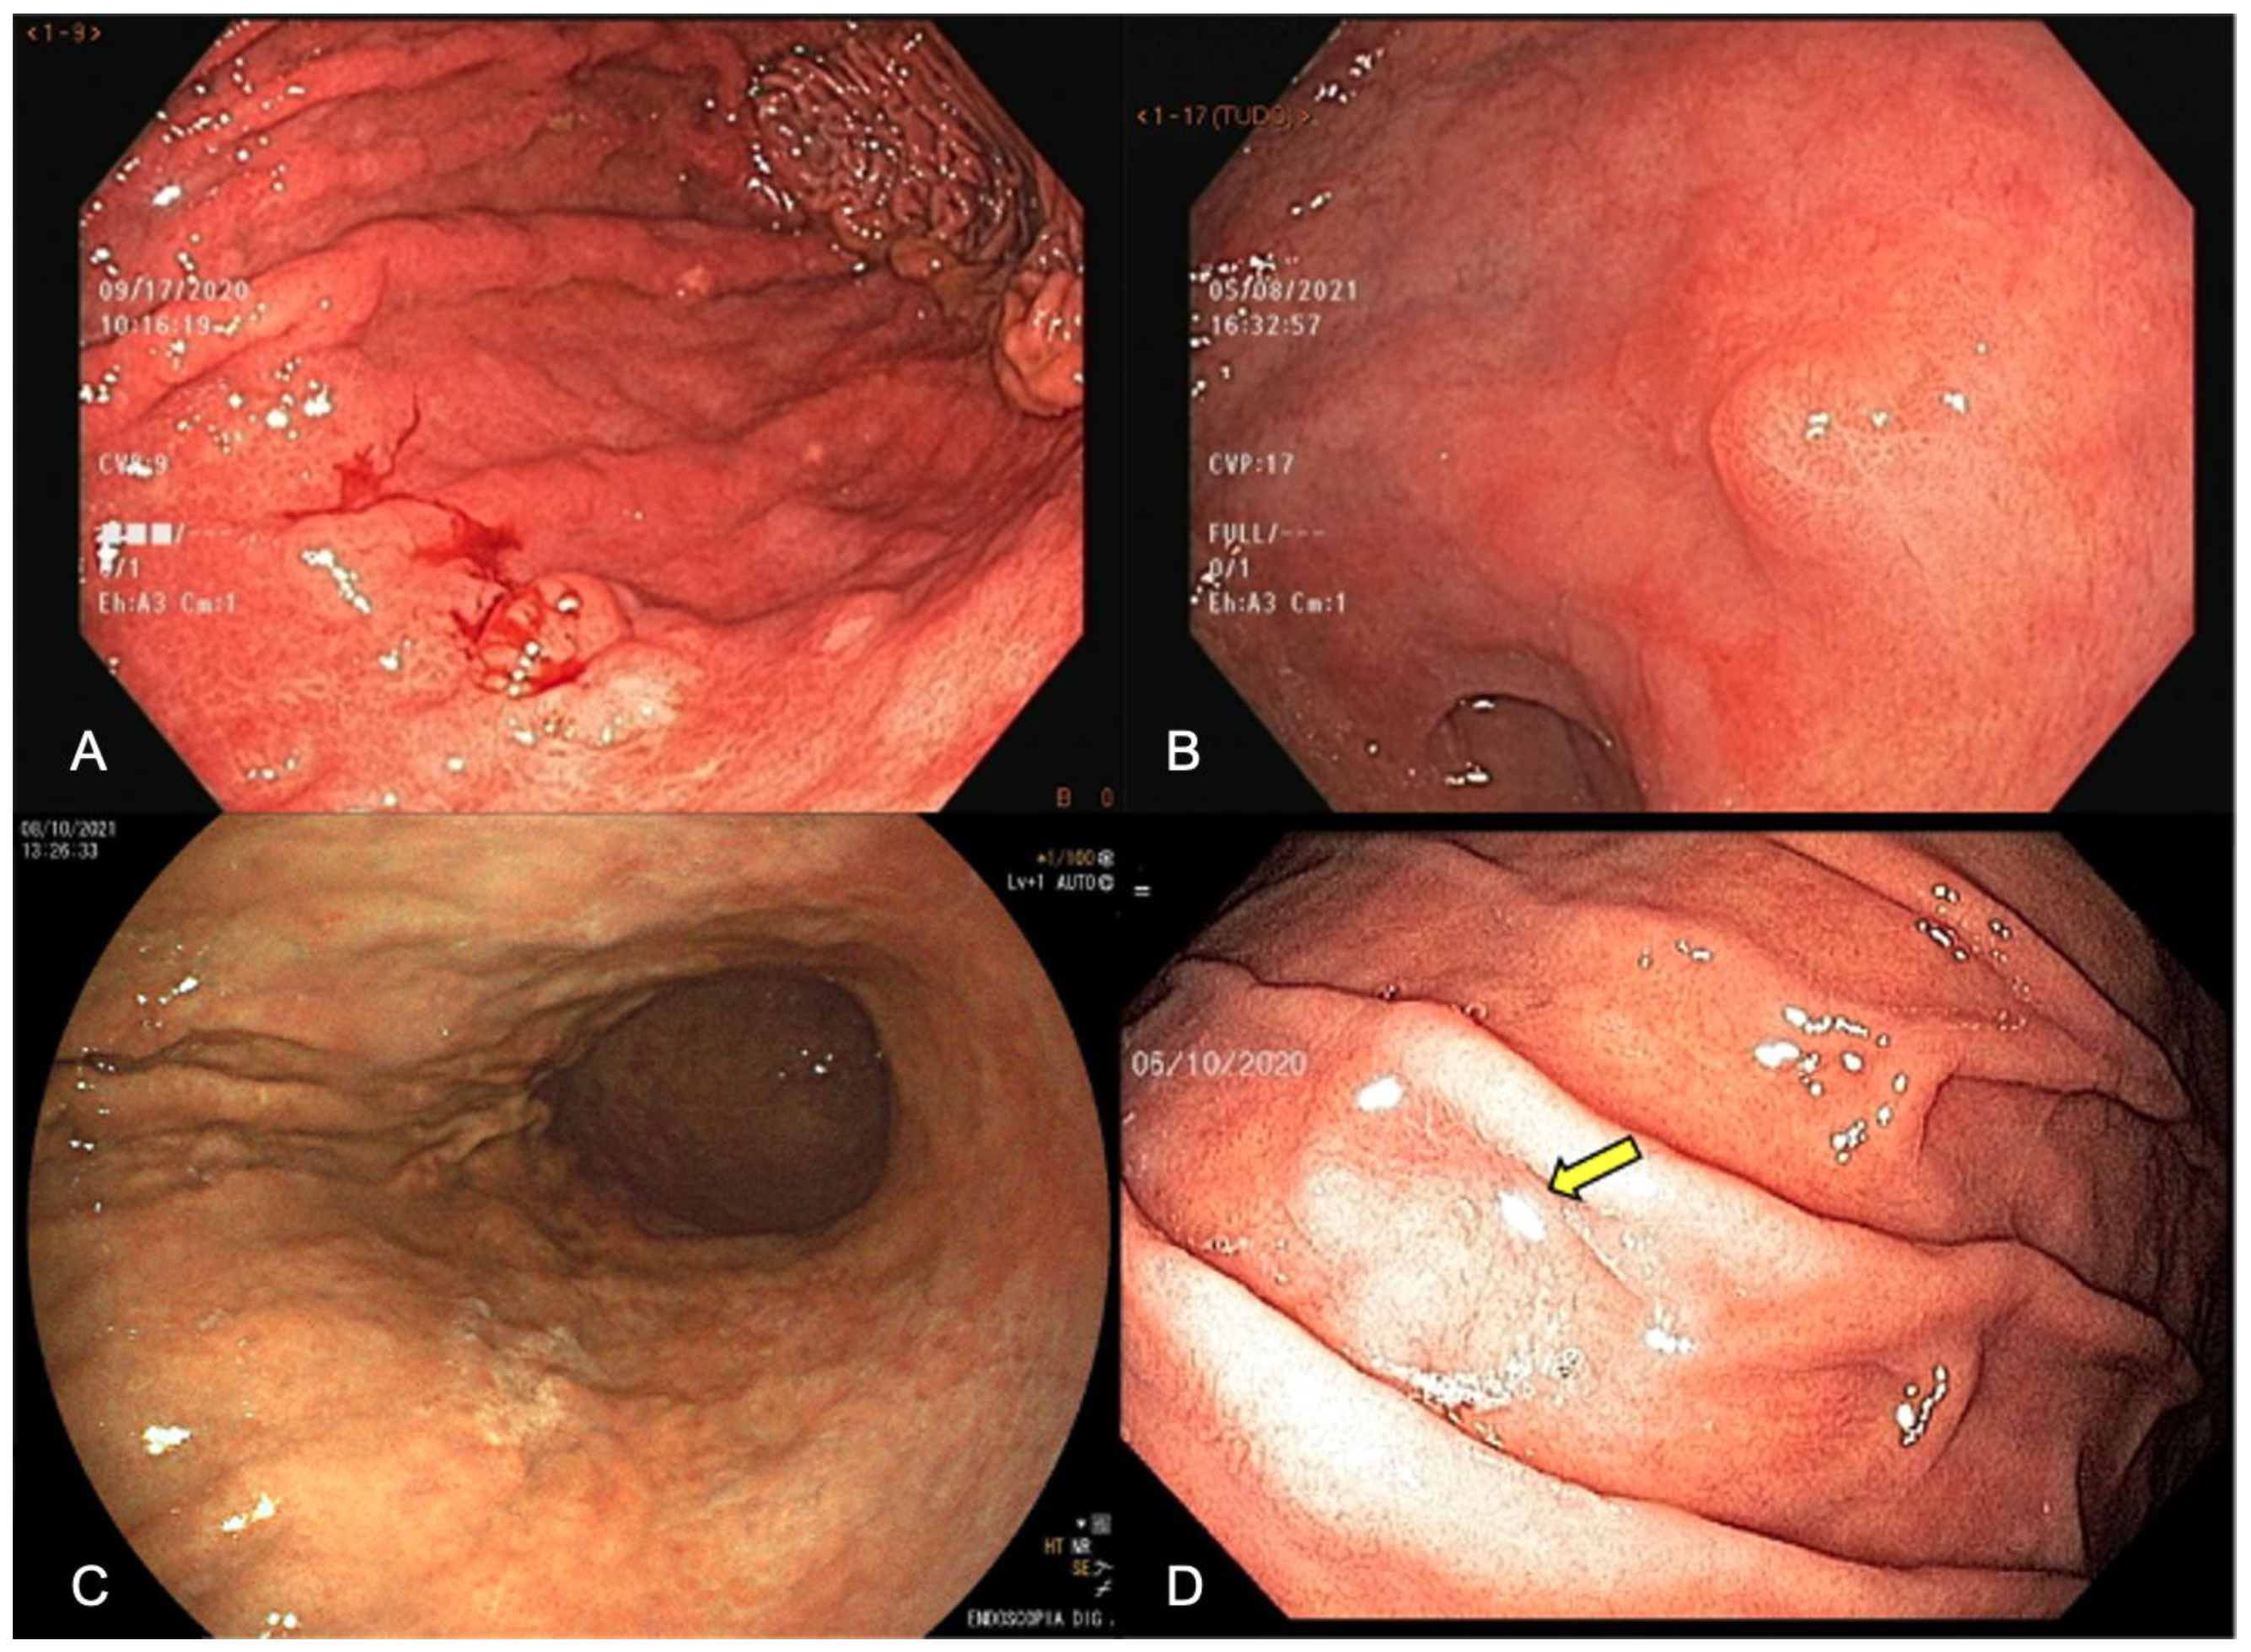

3. White-Light Endoscopy (WLE)

3.6. Target Biopsies of Suspicious Lesions

4. Chromoendoscopy